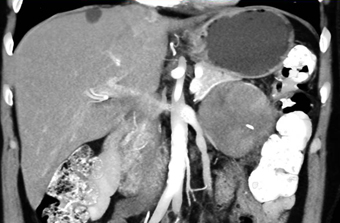

In this patient referred for a pancreatic mass the final dx was?

CTisus Quiz   CTisus Quiz

neuroendocrine tumor pancreas

adrenal carcinoma

GIST tumor

SPEN tumor